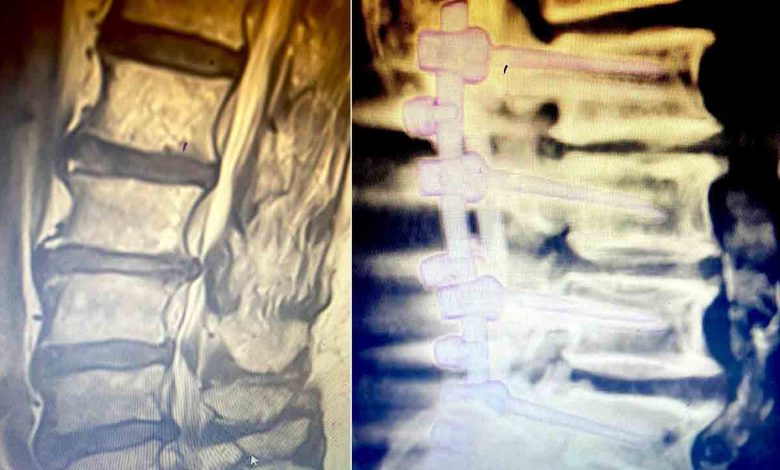

Operasyon hakkında bilgi veren Op. Dr. Serkan Zengin, “Cerrahi tedavide kişinin hastalık seviyesine göre bir operasyon planlanmaktadır. Farklı seviyelerde sıkışma ve kemik daralması varsa büyüyen kemik dokusu küçültülür, omurga kanal çapı genişletilerek sıkışan sinirlerin üzerindeki baskı azaltılır ve vidalarla omurga sabitlenir. Platin vidalar ameliyattan sonra 6 hafta süre içerisinde kemik ile kaynaşmaktadır. Böylece omurga taşıyıcı işlemine de devam edebilir. Ameliyattan sonra, genellikle hasta 2 gün içerisinde taburcu edilir. Operasyon sonrasında beli zorlayıcı hareketlerden ağır kaldırmaktan ve darbelerden hastanın kendini koruması gerekmektedir” dedi. Ameliyat esnasında hastaya yüksek teknolojiden faydalanarak navigasyon ile vida atılabildiğini kaydeden Zengin, “Operasyon esnasında tomografi çekilerek kontrol mekanizmamız ameliyathanede tamamlanmaktadır. Bu yüksek teknoloji ve deneyimli eller ile birlikte komplikasyon riskini sıfıra yakın bir seviyeye indirebilmektedir” diye konuştu.